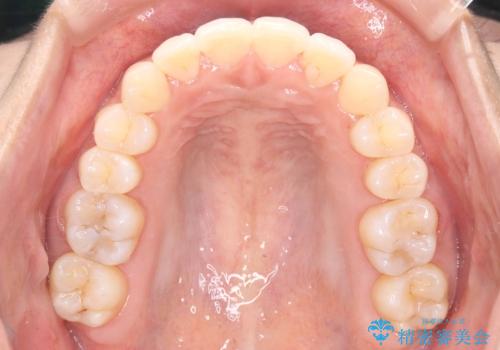

- 歯のデコボコ(叢生)を主訴にご来院された患者様です。

精密矯正検査を行った結果、歯を抜かずに行う、非抜歯のワイヤー矯正で治療を行う方針となりました。

歯並びの乱れに加え、**反対咬合(上下のかみ合わせのズレ)**も認められたため、見た目だけでなく、かみ合わせの改善も同時に行っています。